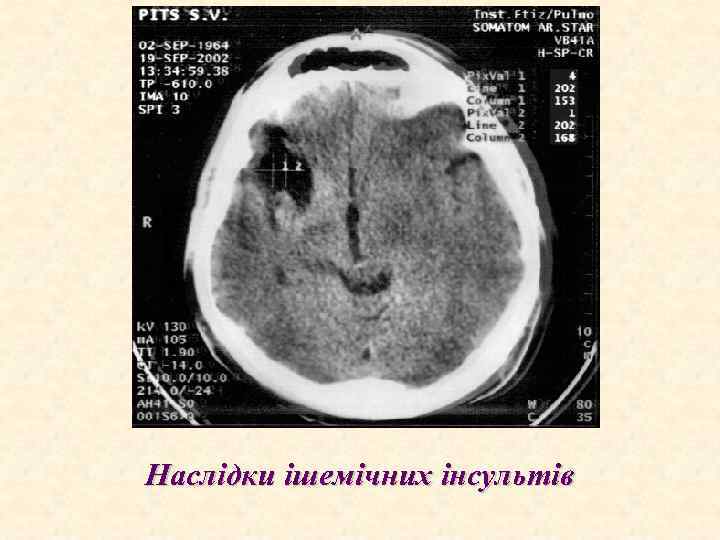

Наслідки ішемічних інсультів

European Society of Cardiology ЕНДОКАРДИТИ Ускладнення ІЕ 1. Серцеві ускладнення: а) застійна серцева недостатність; b) абсцеси міокарда; с) перикардити з тампонадою серця; d) інфаркт міокарда; е) розриви хорд, папілярних м'язів; f) круговий абсцес аортального (мітрального) клапана; 2. Позасерцеві ускладнення (в тому числі і внаслідок емболій): а) ниркові: інфаркти нирок, гломерулонефрит (фокальний, дифузний), абсцеси, кортикальний некроз, ниркова недостатність; b) неврологічні і психіатричні: мозковий інсульт (емболічний, геморагічний), інтоксикаційна енцефалопатія (головний біль, запаморочення, сплутаність свідомості, дезорієнтація, психози; корсетний больовий парез, мононеврити); с) спленальні: інфаркт, абсцес, розрив; d) мікотичні аневризми; е) легеневі емболії, інфаркти, пневмонії, абсцеси